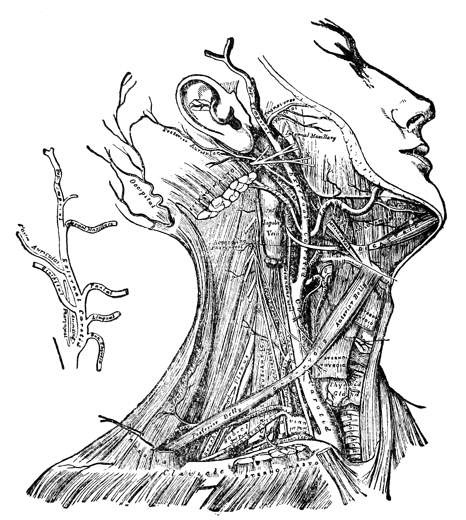

Fig. 3—Lymphatics of the head and neck.

B, the thoracic duct.